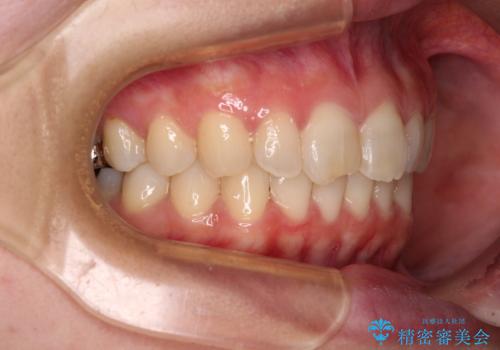

- 近々転勤の予定があるが、早めにインビザラインによる矯正治療を始めたいとのことで来院された患者様です。

上下ともにデコボコの程度は著しいものではなく、インビザラインで十分に対応可能な歯列不正でした。

後戻りによりスペースができてしまうことを避ける目的で、IPR(歯と歯の間を削る)を極力用いない矯正治療を行うこととしました。

インビザラインであれば来院間隔が多少長くなってもワイヤー矯正ほど問題とならないため、遠方からの通院であっても中断や転院せずに治療を行うことができます。